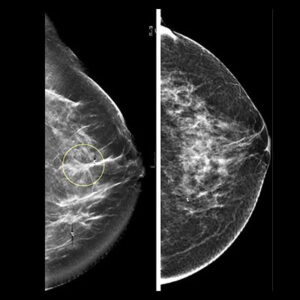

At NM PET CT Imaging Centre, we offer advanced digital mammography for early detection of breast abnormalities, including breast cancer. Our safe, low-dose imaging and expert radiologists ensure accurate results in a comfortable, supportive environment. Regular breast screening is key to timely diagnosis and better outcomes.